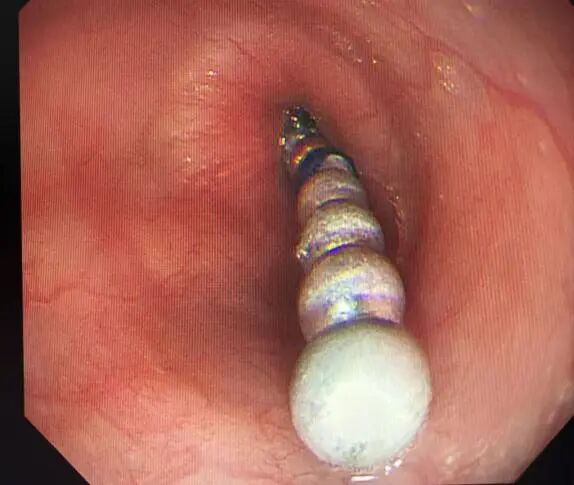

万幸的是

医院内镜团队

在麻醉科的配合下

紧急实施胃镜探查

15枚磁珠被安全取出

医生会通过相关检查确定异物位置,再根据异物的性质和位置,选择安全、合适、有效的治疗方案。随着内镜技术的发展,约90%的上消化道异物可通过内镜微创取出。